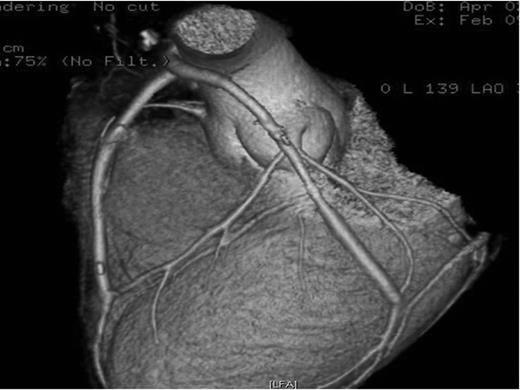

A 31-year-old male, airline pilot, with no clinical history or cardiovascular risk factors, was admitted to the emergency room with 12 h history of retrosternal chest pain radiating to the jaw and upper extremities, during a trans-Atlantic flight, which did not improve with analgesia. Because of persistent pain, he came to our hospital. Upon arrival to the emergency room, his vital signs were stable and he had a normal physical examination but complained of precordial pain. The cardiac enzymes were elevated and the EKG detected S-T changes consistent with MI (Fig. 1). A multidetector CT coronary angiography was performed showing left main trunk dissection with 50% stenosis (Fig. 2).

Multidetector coronary angio-tomography reveals dissection at the ostium of the left main coronary artery. A, aorta; LMCA, left main coronary artery; arrow, dissection.

The patient underwent emergent coronary revascularization with saphenous vein grafts to the first obtuse marginal and the left anterior descending artery (LAD). His postoperative course was uneventful and the patient was discharged home 7 days later. Control CT coronary angiography was performed 2 months later revealing patent aorto-coronary grafts (Fig. 3).

CT coronary angiography reconstruction showing patent grafts to the LAD and obtuse marginal arteries.